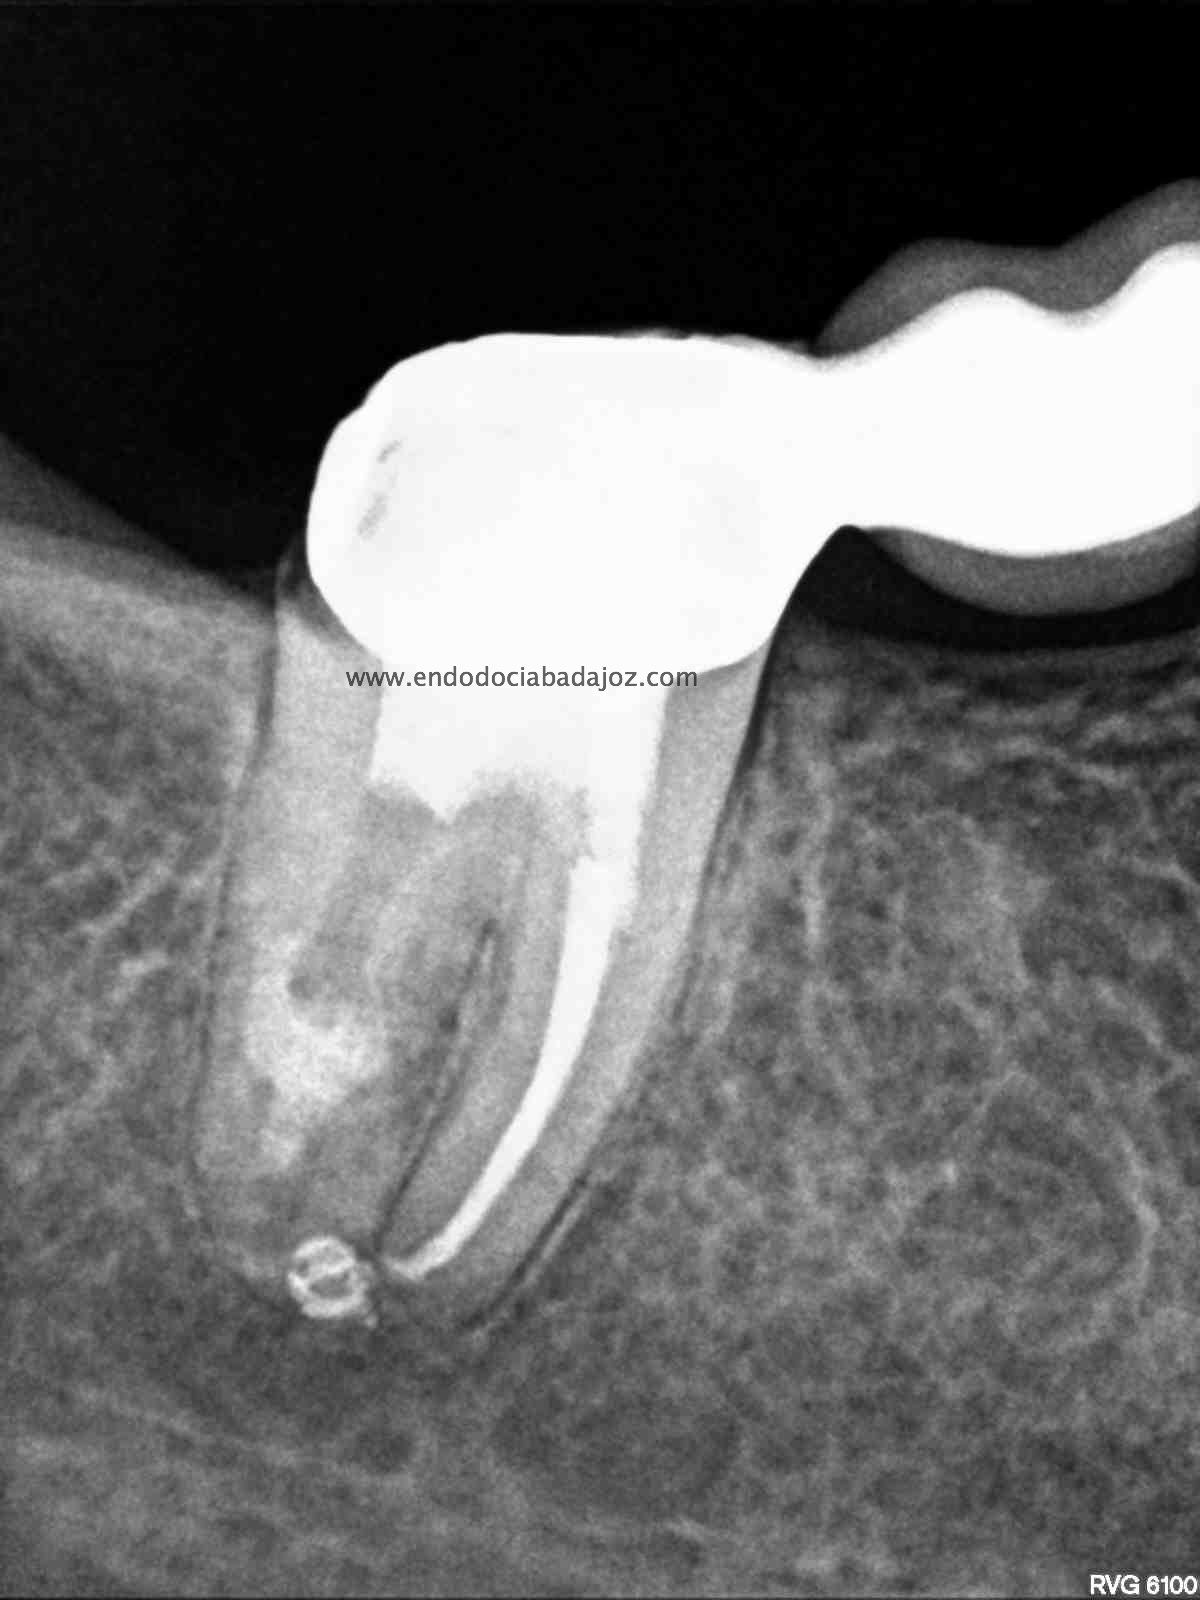

Acude a nuestra clínica una paciente que llamamos a revisión después de realizarle un retratamiento endodóntico de la pieza 4.7 hace unos meses. Si recordamos el día que llegó, no se nos presentaba muy bien el caso, y como otros muchos casos, intentamos retratarlo, pues pensamos que podríamos manejarlo.

Con ayuda del microscopio, pudimos confirmar que se trataba de una reabsorción interna en el tercio medio y una reabsorción radicular del conducto distal.

Bueno, pues el conducto distal se obturó en su tercio apical y medio con M.TA.

Hemos llamado a revisión a la paciente en varias ocasiones ( 6 meses y 9 meses)

(revision a los 6 meses) (revisión a los 9 meses)

Como podemos observar, la lesión periapical ha regenarado: